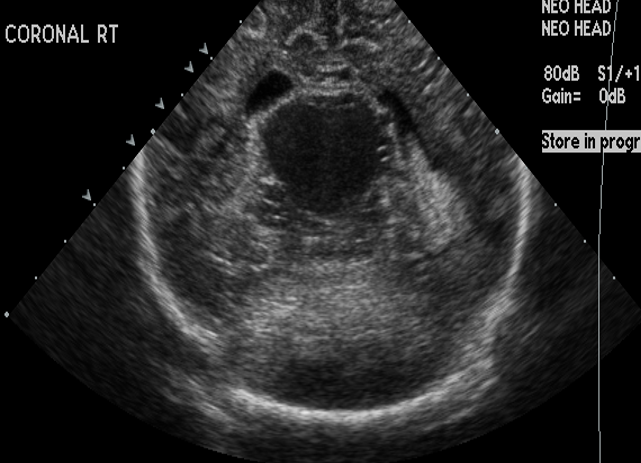

Info Images Findings Impression Reco/Acuity Case Images View Images / Launch Visage Case Notes History Full term infant. We are asked to evaluate posterior fossa cyst. Exam Gray scale and Doppler Ultrasonographic examination of the head. Prior Study N/A Dicom View Reference Material

Section 1 Submit Findings Case149 Findings Brain The brain is immature. Yes No There is under-sulcation and open sylvian fissures. Yes No There is/are multiple hypoechoic areas in the periventricular white matter. Yes No There is/are multiple hyperechoic areas in the periventricular white matter. Yes No There is diffuse cerebral edema with diffusely increased echogenicity of the brain parenchyma and loss of grey white matter differentiation. Yes No The thalami/basal ganglia are hypoechoic. Yes No There is periventricular calcification. Yes No There is intra-parenchymal calcification. Yes No CSF spaces/ventricular system There is a prominence of the extra axial fluid spaces. Yes No There are debris/septations in the extra axial fluid spaces. Yes No There are debris/septations in the ventricles. Yes No There is a subdural collection on the right/left side. Yes No There is prominence of the ventricular system. Yes No There is an asymmetry of the ventricular system. Yes No There is a cavum septum pellucidum. Yes No There is a midline shift towards right/left. Yes No The choroid plexus is bulky/lobulated. Yes No There is a choroid plexus cyst measuring… Yes No There are debris/clots in the occipital horn. Yes No There is a posterior fossa cyst measuring… Yes No The tentorium is elevated/depressed. Yes No The lateral ventricle/s are dilated. Yes No The third ventricle is dilated. Yes No The 4th ventricle is dilated. Yes No There are pseudo cysts. Yes No Germinal matrix hemorrhage (Only in the premature infants): Please do not answer if the patient is a full term. There is a germinal matrix hemorrhage, consistent with a grade I hemorrhage. Yes No There is an intraventricular extension consistent with a grade II hemorrhage. Yes No There is an intraventricular extension with the dilatation of ventricles, consistent with a grade III hemorrhage. Yes No There is an intra-parenchymal extension, consistent with grade IV hemorrhage. Yes No On color Doppler examination, the Resistive index in the anterior cerebral artery is… There is a loss of the diastolic flow on the Doppler exam. Yes No There is altered vascularity on Doppler imaging. Yes No There is an AVM in the region of… Yes No